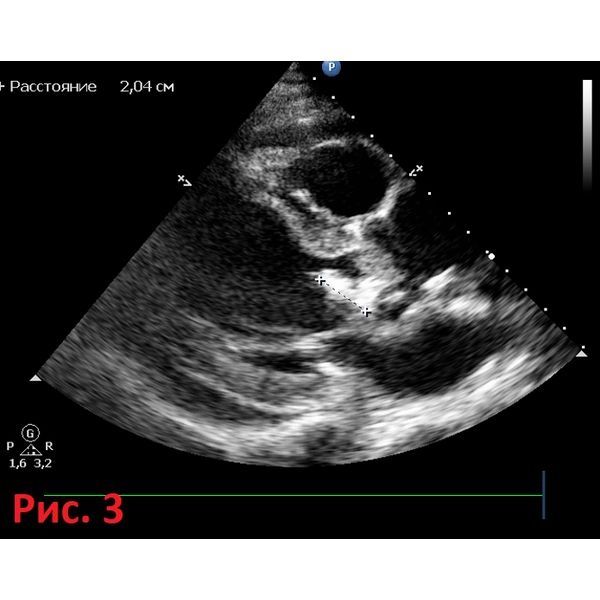

Эхокардиография показала:

- недостаточность аортального и митрального клапанов;

- наличие подвижных гиперэхогенных образований створок клапанов (светлых участков на снимке);

- дилатацию (расширение) левых отделов сердца.

Также у мужчины был пансистолический шум в сердце (признак митральной недостаточности).